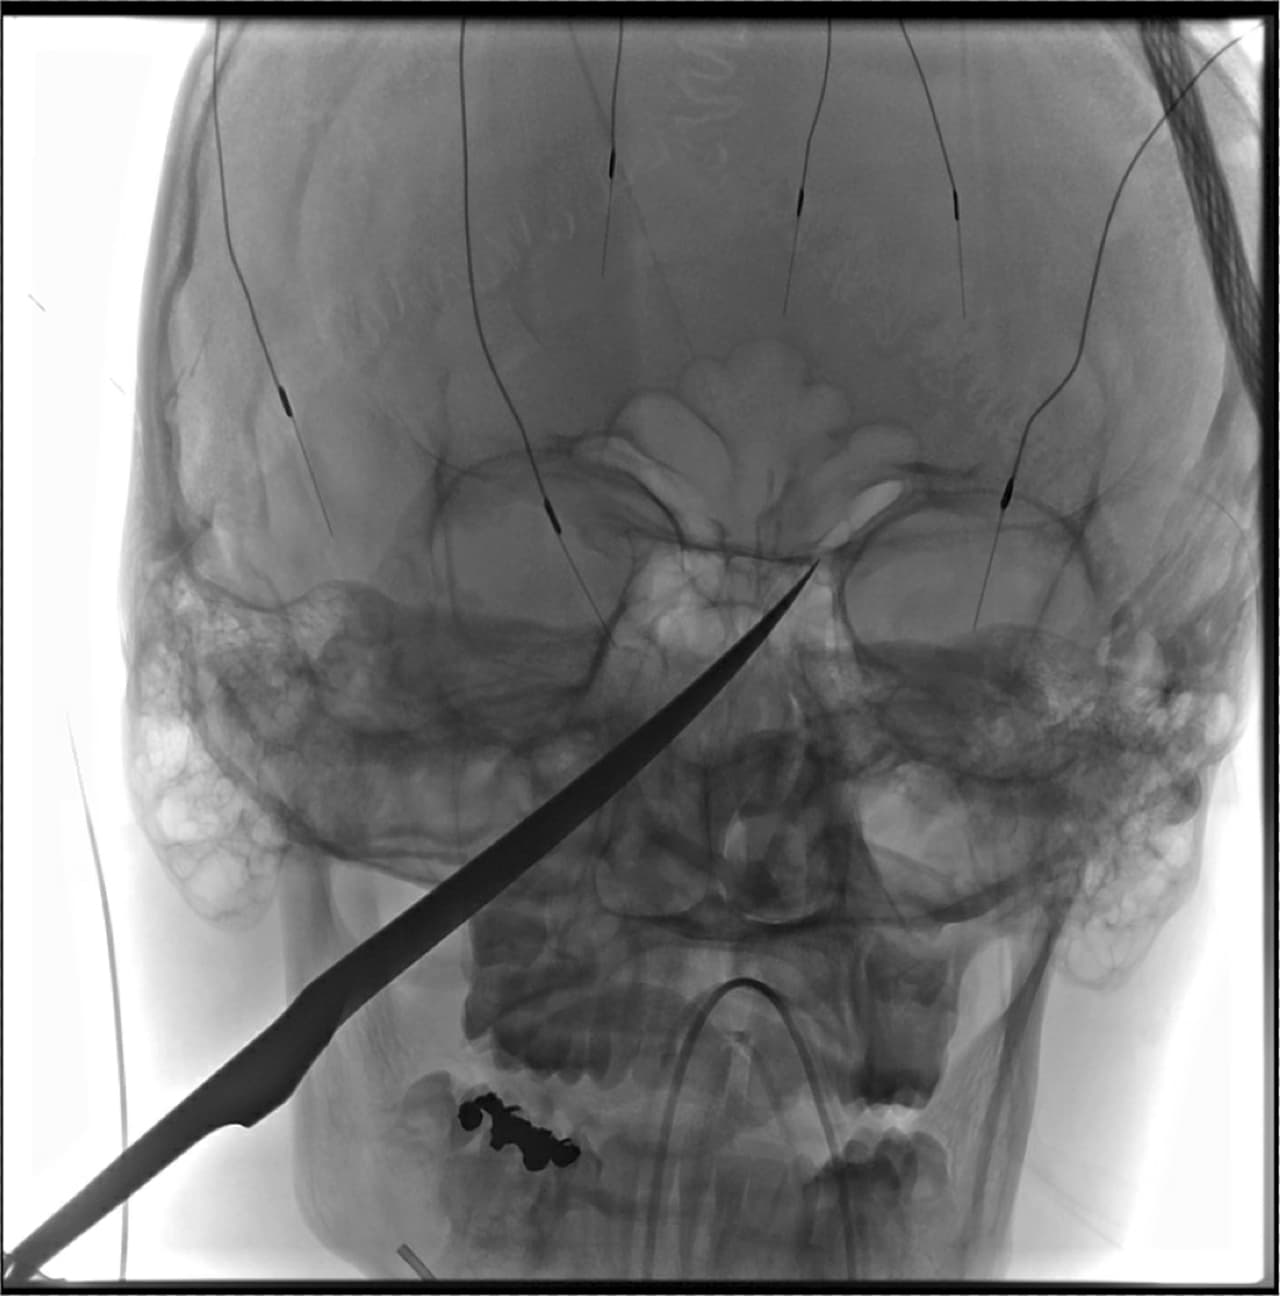

Una imagen de rayos X mostraba la profundidad de la herida de en la cara de Eli Gregg: la hoja del cuchillo estaba clavada en su cráneo y alcanzaba hasta justo debajo de su cerebro; la punta del arma presionaba su arteria carótida, que abastece de sangre al cerebro.

Los médicos se prepararon para una posible hemorragia cerebral, pero la operación se realizó sin problemas y la arteria permaneció intacta. Ebersole y sus colegas utilizaron catéteres, globos diminutos y otras herramientas para extraer el arma cuidadosamente.